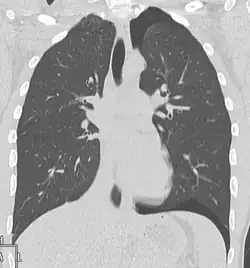

Verletzungen der Lunge können neben einer Lungenkontusion als Quetschverletzung Lungenrisse sein. Letztere führen zu einem Pneumothorax, wie er bei 10 bis 50 Prozent der Patienten mit Thoraxtrauma auftritt,[6] und gegebenenfalls zu einem Spannungspneumothorax. Blutungen in den Thorax hinein führen zu einem Hämatothorax. Bei einem Hämatopneumothorax treten sowohl ein Pneumo- als auch ein Hämatothorax in Kombination auf. Symptome sind zunächst Luftnot und je nach Ausmaß der Blutung auch Kreislaufinstabilität. Bei einem Pneumothorax kann sich insbesondere bei Ausbildung eines Spannungspneumothorax ein Hautemphysem bilden, das eine große Ausdehnung erreichen kann. Therapie ist eine Entlastung der Pleurahöhle mittels Thoraxdrainage auf der betroffenen Seite. Üblicherweise kommen kleinere intrathorakale Blutungen von alleine zum Stehen, so dass außer einer Drainage keine weiteren Maßnahmen notwendig werden. Eine Thorakotomie zur operativen Blutstillung kann bei einem initialen Blutverlust von mehr als 1.500 ml nach der Thoraxdrainage oder bei einem fortwährenden Blutverlust von mehr als 250 ml pro Stunde über mehr als vier Stunden erfolgen.[2][5]

Thorako-abdominelle Verletzungen

Die Kombinationsverletzung von Thorax und Abdomen ist die vierthäufigste Kombination bei mehrfachverletzten Patienten.[2] Insbesondere Zwerchfell, Leber und Milz sind auch bei isolierten Thoraxtraumen oft mitbetroffen. So können beim stumpfen Thoraxtrauma gebrochene Rippen in Leber oder Milz spießen und starke Blutungen verursachen. Durch ein plötzliches Kompressionsereignis kann das Zwerchfell ein- oder beidseits rupturieren und es kann zur Verlagerung von Bauchorganen in den Brustkorb kommen. Hierbei kommt es zu einer mechanischen Kompression der Lungen mit Luftnot und abgeschwächtem Atemgeräusch auf der betroffenen Seite. Bei einer rechtsseitigen Zwerchfellruptur liegt mit sehr großer Wahrscheinlichkeit auch eine schwere Verletzung der Leber vor.[2] Bei penetrierenden Thoraxtraumen können die in den Körper eindringenden Fremdkörper wie Projektile oder Messer sich bis in den Bauchraum bewegen und dortige Organe mitverletzen.[2] Symptome von intraabdominellen Organverletzungen sind Schock und Anzeichen eines akuten Abdomens.[2]